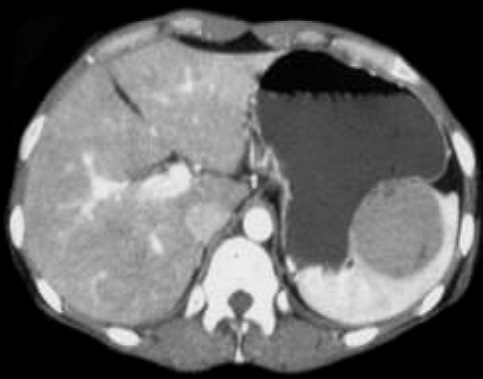

Image radiologique TDM en coupe

axial du splenomegalie d'une cirrhose du foie . La

rate est volumineuse ,a isodense , sa diametre

anterieuse - posterieuse depasse 11cm ,systeme veine

splenique est distendue . Le foie droit est a bord

crenele , reduction de volume , systeme veine porte

est distendue et en presence de l'ascite peritoneale |